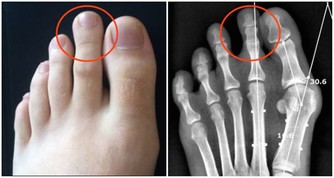

最突出的信號就是皮膚出現粗糙、變黃和長斑,指甲也會變得凹凸不平。